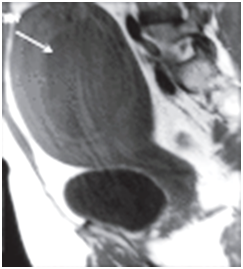

The place of MRI in the pre-operative diagnosis cannot be overemphasized.14–16 The images below from MRI using T1 T2 weighted views delineate the origin of cystic mass better than other imaging techniques and should be well applied were appropriate in the preoperative management of patient’s with massive cystic swelling of the abdomen. The cost implication and inaccessibility of this tool limits the use in routine gynaecological practice (Figure 5) (Figure 6).